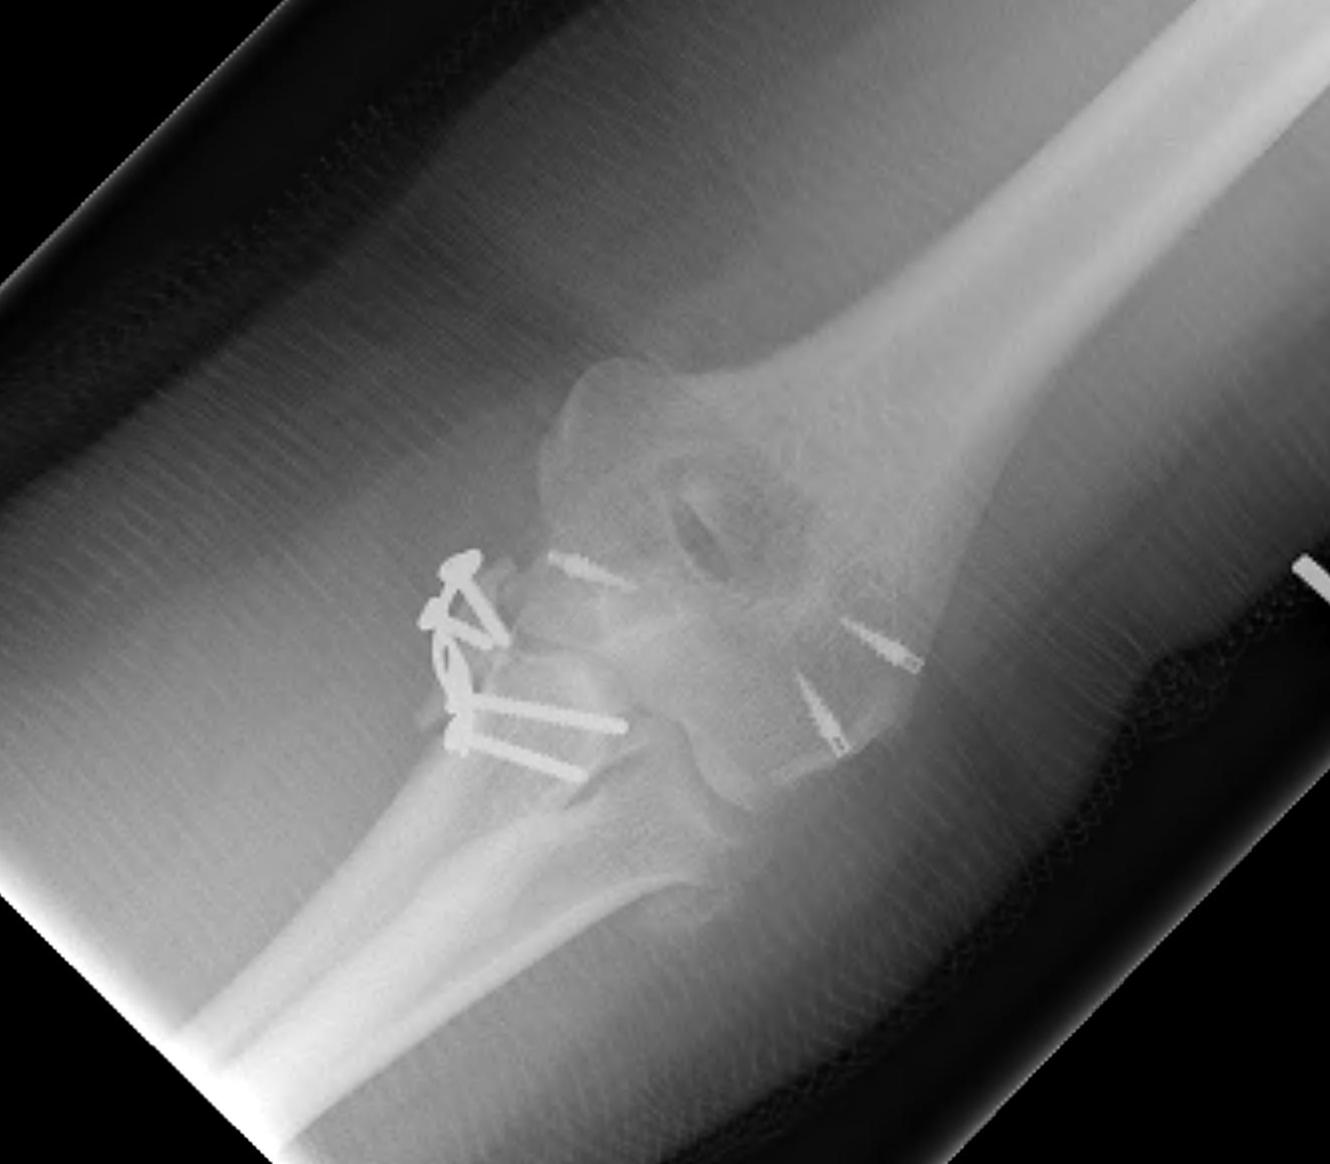

Terrible Triad

Definition

Elbow dislocation with radial head fracture + coronoid fracture + MCL tear

Principles

1. Restore coronoid stability - ORIF type II / III, suture repair type I

2. Restore radial head stability - radial head ORIF or arthroplasty

3. Restore lateral stability - LCL repair and common extensor origin +/- reconstruct +/- internal brace

4. +/- Restore medial stability - repair MCL if residual stability

5. +/- External fixation / internal joint fixation

| Type II / Reconstructable radial head | Type III / Radial head arthroplasty |

|---|---|

|

Lateral / Kocher approach - ORIF radial head with screws/ plate - LCL +/- common extensor origin repair - reassess stability |

Lateral / Kocher / Kaplan / EDC split approach - excise radial head - can suture small coronoid process fracture through gap - radial head replacement - LCL +/- common extensor origin repair - reassess stability

Unstable - medial approach - FCU split / over the top approach to coronoid process - ORIF coronoid process with sutures / buttress plate / screws - MCL repair +/- common flexor origin repair - reassess stability |

| Unstable - external fixation | Unstable - external fixation |